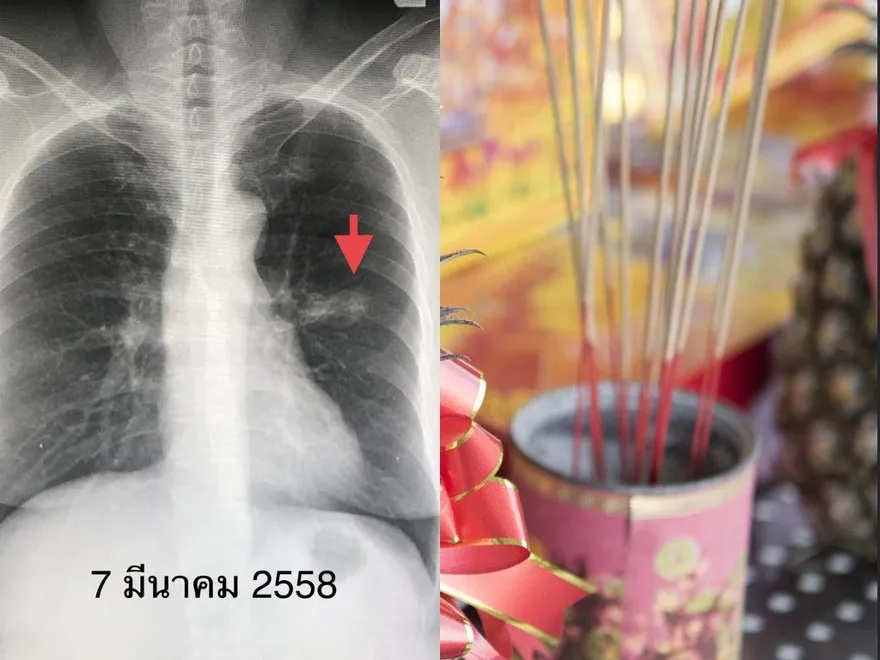

肺癌

燒香